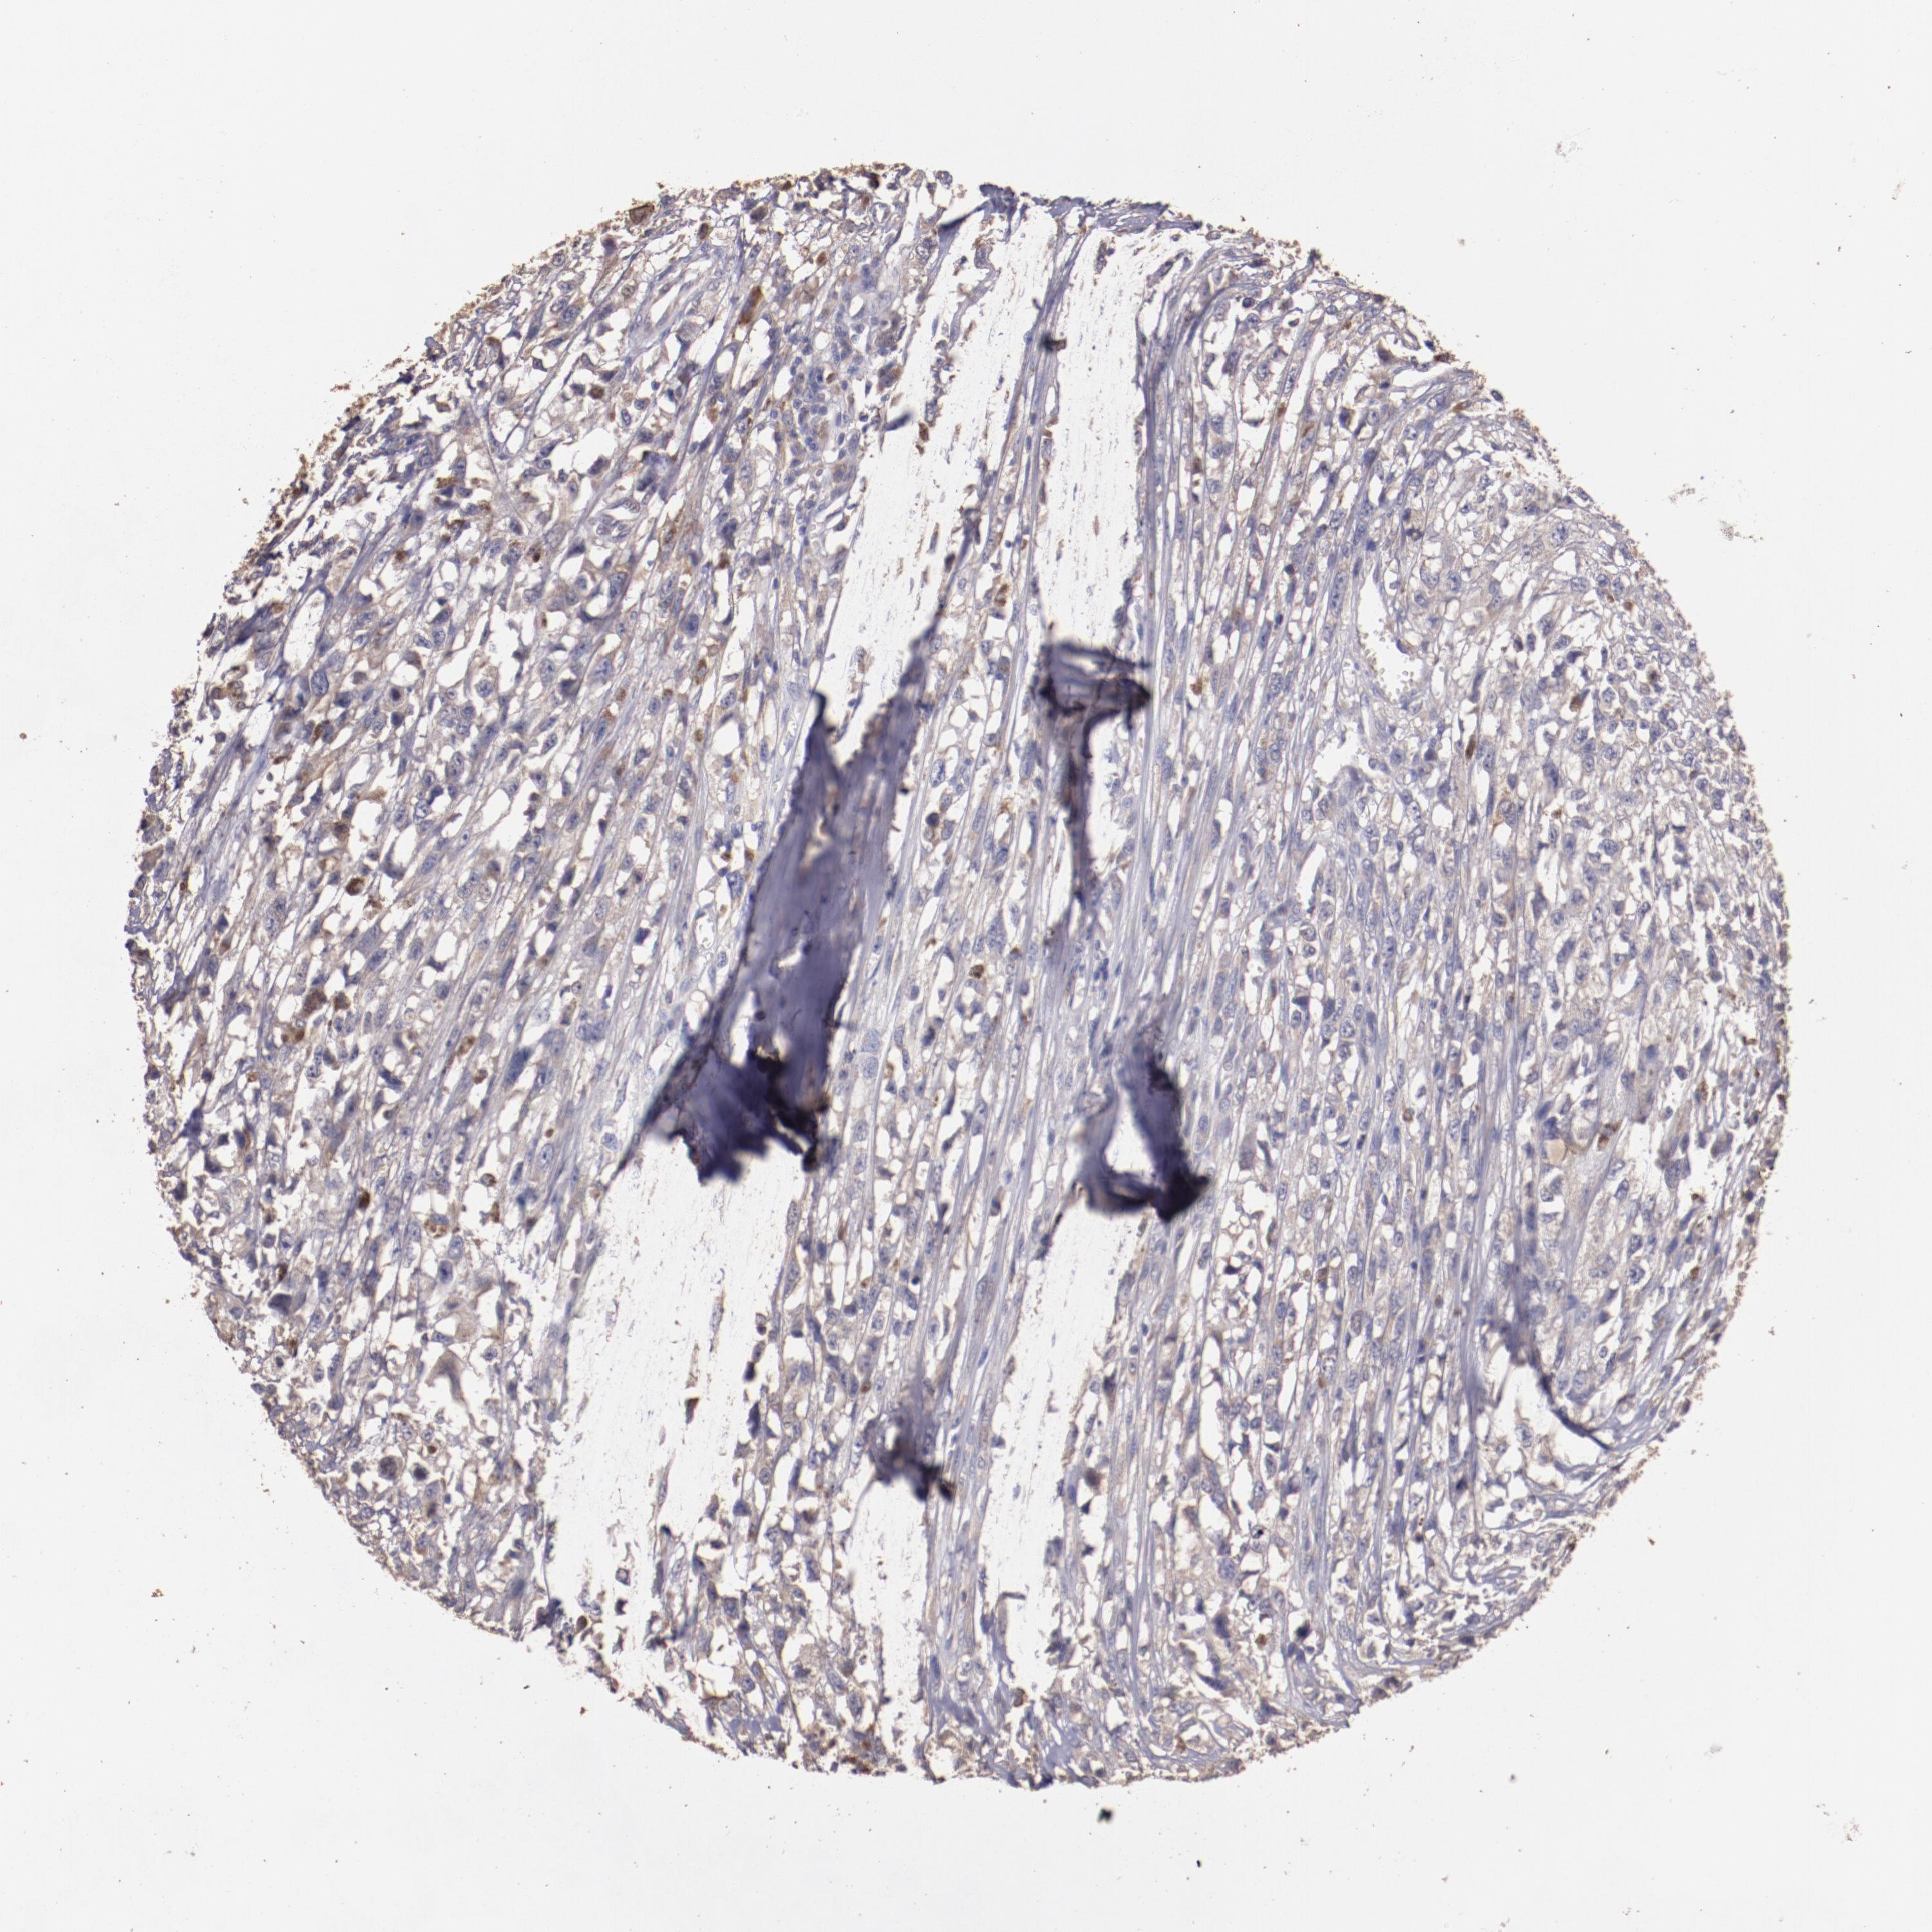

MELANOMA - Protein expressioni

A mouse-over function shows sample information and annotation data. Click on an image to view it in a full screen mode. Samples can be filtered based on level of antibody staining by selecting one or several of the following categories: high, medium, low and not detected. The assay and annotation is described here.

Note that samples used for immunohistochemistry by the Human Protein Atlas do not correspond to samples in the TCGA dataset.

Antibody stainingi

Antibody staining in the annotated cell types in the current human tissue is reported as not detected, low, medium, or high, based on conventional immunohistochemistry profiling in selected tissues. This score is based on the combination of the staining intensity and fraction of stained cells.

Each image is clickable and will lead to virtual microscopy that enables deeper exploration of all samples and also displays staining intensity scores, fraction scores and subcellular localization as well as patient and tissue information for each sample.

Antibody HPA002945

Staining

High

Medium

Low

Not detected

Intensity

Strong

Moderate

Weak

Negative

Quantity

>75%

75%-25%

<25%

None

Location

Nuclear

Cytoplasmic/membranous

Cytoplasmic/membranous,nuclear

Malignant melanoma, NOS

Malignant melanoma, Metastatic site